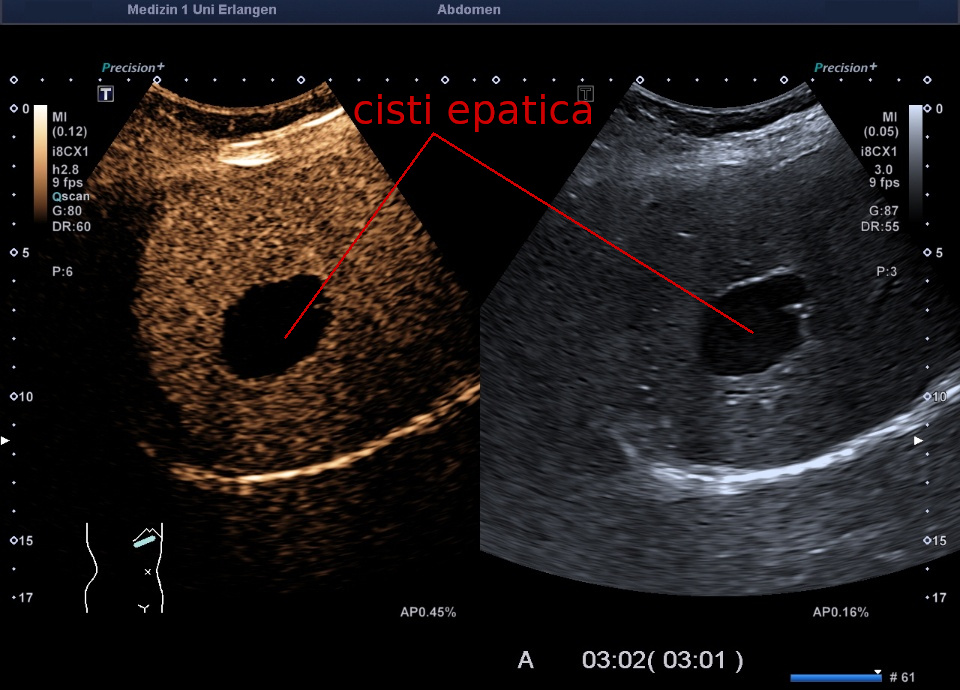

- Cisti epatiche, fegato policistico

Le cisti possono comparire nel parenchima epatico di origine endodermica, nonché nel tessuto epiteliale ectodermico. Entrambi i tipi possono raggiungere dimensioni di diversi cm. In caso di attivazione dei dotti collettori renali, l'effetto può essere intensificato.- Cisti nel parenchima epatico (adenocarcinoma cistico, cisti epatica solitaria): attivazione da fame/esistenza. Residuo riparativo di cancro epatico (adenocarcinoma del fegato).

- Cisti biliare: attivazione da rancore territoriale o di identità. Recidive o riparazione in sospeso.